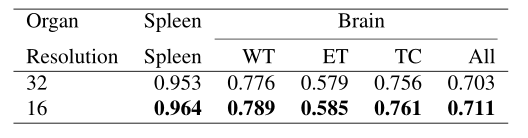

Patch Resolution:较低的输入补丁分辨率导致较大的序列长度,因此内存消耗更高,因为它与分辨率的立方成反比。如表4所示,实验表明,降低分辨率可以持续提高性能。具体来说,将patch分辨率从32降低到16,在脾脏和大脑分割任务的平均Dice得分方面分别提高了1.1%和0.8%的性能。由于内存的限制,没有进行低分辨率的实验。

表4:patch分辨率对分割性能的影响。